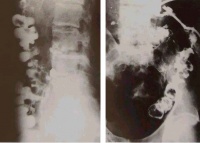

骨结核在X片上的表现

(一)骨质破坏

骨小梁模糊,似磨砂玻璃样的感觉,呈现出骨质缺损。其缺损区为局限性,边缘相对清晰,可有硬化,是为局限性结核病灶的特点,再继续以弥散性破坏加剧,易向髓腔拓展而形成结核性骨髓炎。骨质破坏易发生于骨骺及干骺,可在骨质中央部分亦可在边缘部分,形成缺损,往往骨骺及干骺同时破坏,形成不受骺板限制的统一破坏区。

关节骨质破坏,从两侧边缘开始,中央的关节板面较轻,是结核的特点。但在膝关节、肩关节中央部分亦可破坏,因紧密相接的软骨较少。关节骨质破坏上下相对应的关节板面同时受累。但这种接触面骨质破坏也不一定是为结核所独有。

肩关节结核的肱骨头呈现类圆形穿凿样改变。膝关节结核在胫骨上端关节板面两侧呈现小的穿凿样改变,耻骨结核在耻骨联合或耻骨板呈现类囊状或不规则的破坏。椎体结核以骨质破坏和椎间隙狭窄为主要表现。

常在骨端内或干骺端内见到,中央性破坏可形成囊状,亦可在短骨及块状骨见到,甚至在骶骨上显示囊状破坏区。

死骨的形成一般较多见的为细小的沙砾样死骨,常在松骨破坏区发现,如骨骺内,干骺内。髌骨结核亦常出现死骨,血供丰富的地方不易见死骨,如骨干结核、髂骨结核。有时在上下相对应的关节面都有死骨,常称之为接触性死骨。在膝关节内时有发生。

(二)骨形改变。管状长骨的破坏可表现为不同程度的膨胀变形,脊椎的椎体结核、椎体坍塌可呈楔状变形,椎体上下之间相互嵌入出现驼背或龟背畸形等。

(三)关节改变。关节软骨被破坏可使关节间隙狭窄,软骨破坏后不会再生,狭窄发生后会长期存在。脊椎椎间盘破坏不能再生,如破坏明显,椎间隙永久性消失